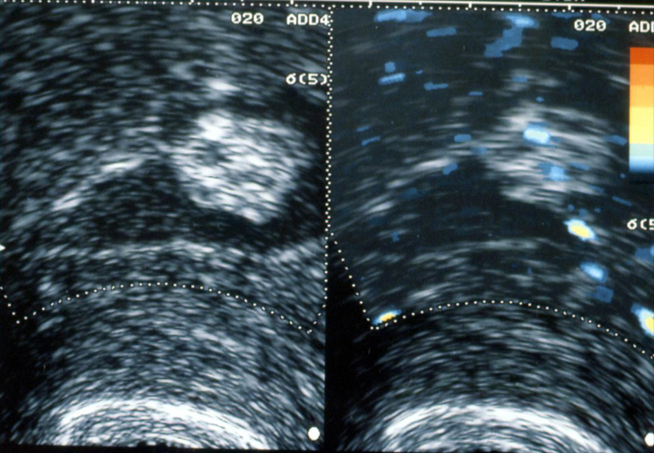

Hystérosonographie. Polype muqueux